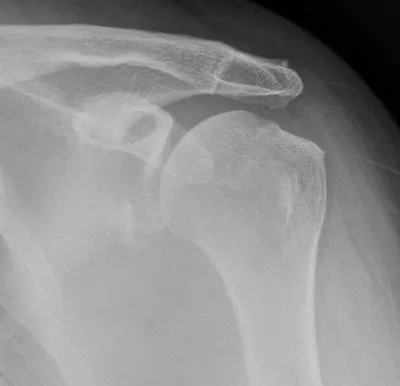

Supraspinatus bursal surface partial tear seen on bursography

USShoulderTendon Injury+1